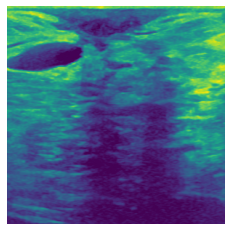

In figure 3, we present qualitative examples of different masking strategies. It is observed that, unlike context prediction and restoration, our method tends to propose targeted masks like the tumor regions or regions with abnormalities and avoids masking less helpful regions. However, it should be noted that Intelligent-Masking does not necessarily mask the tumor regions but considers all areas of interest that results in better feature learning. Examples of other masking samples are provided in supplementary materials. Furthermore, in medical images, unlike natural scenes, the structures are very local with imbalanced information throughout an image. Therefore, random masking strategies as shown in Fig 3 operate ineffectively by masking non-informative regions.

(a) Original

(b) Intelligent-Masking

(c) Context Prediction

(d) Context Restoration

Figure 2: Qualitative examples of compared method’s strategies for masking